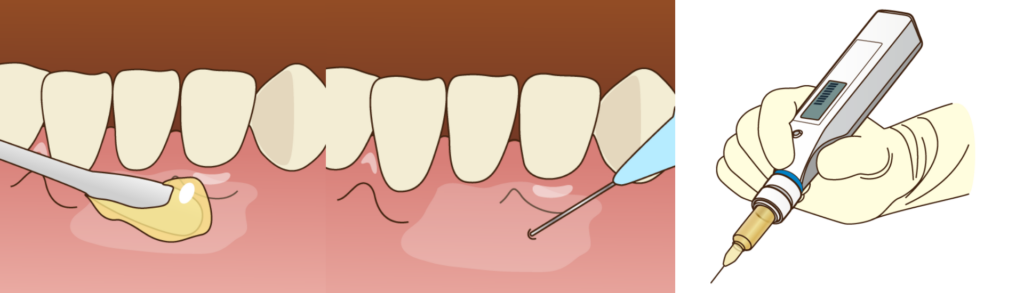

痛みを最小限に抑えるために

「抜歯は痛い」というイメージをお持ちの方は多いですが、手術中は局所麻酔が効いているため痛みを感じることはありません。

当院では、この麻酔の痛み自体も軽減するために表面麻酔(塗り薬)や電動麻酔器を使用し、細心の注意を払って麻酔を行います。また、歯科恐怖症の方や親知らずを一度に4本抜きたいという方には、医科と連携した「静脈内鎮静法(セデーション)」をご提案することも可能です。

点滴から鎮静薬を投与することで、うたた寝をしているようなリラックスした状態で手術を受けていただけます。

「気づいたら終わっていた」と感じる方がほとんどで、心身のストレスを大幅に軽減できる方法です。

麻酔・抜歯手術

表面麻酔と局所麻酔を行い、十分に効いたことを確認してから手術を開始します。簡単なケースであれば数分で終わりますが、骨に埋まっている場合は歯茎を切開し歯を分割して取り出します。術中は定期的にお声がけをし、体調の変化がないか確認します。

止血・縫合

歯を抜いた穴をきれいに清掃し、ガーゼを噛んで止血します。切開した場合は糸で縫い合わせます。お薬(抗生物質・痛み止め)を処方し、術後の注意点をご説明して終了です。